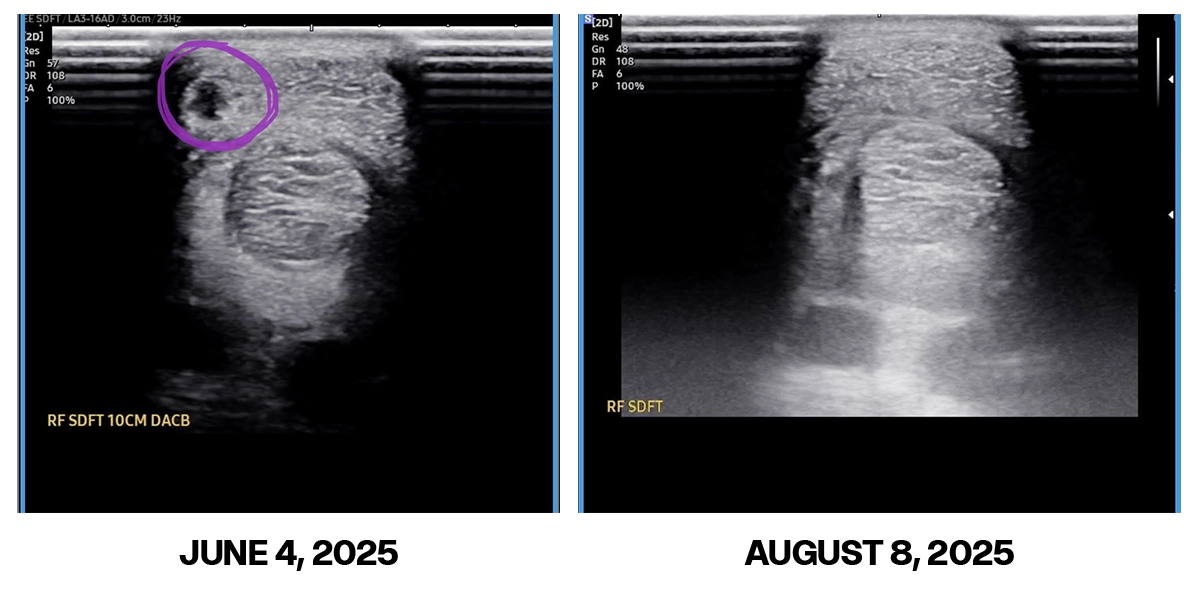

These photos are 8 weeks apart.

Photo 1: June 4, grade 2.5/5 SDFT tear front leg

Photo 2: August 8, can’t find the tear, vet was absolutely bewildered, figured it was already at least 80% healed up In only 8 weeks! Anyone whos healed a soft tissue injury knows thats extremely quick!

For context: this is on a 18 year old rodeo horse that has been kicked out to pasture on holidays since initial diagnosis, 0 rehabbing walks/workouts.